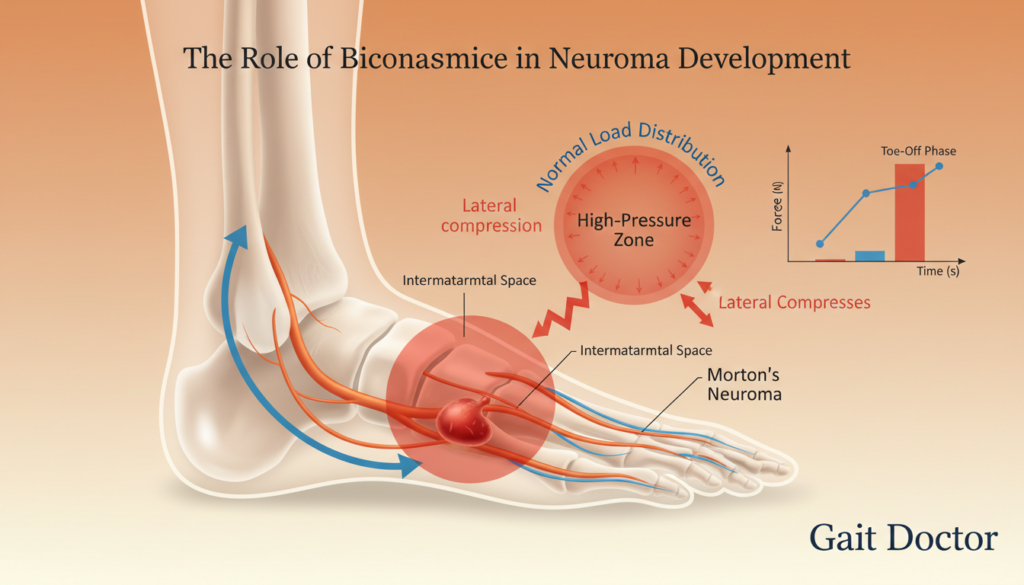

The Role of Biomechanics in Neuroma Development

Foot biomechanics is very important in Morton’s Neuroma. Bad foot mechanics can press on nerves, leading to this condition.

Foot Mechanics and Nerve Compression

The nerve between the toes can get squished if the foot doesn’t move right. Poor foot mechanics put more pressure on the nerve. This causes the pain and numbness of Morton’s Neuroma.

Gait Patterns That May Contribute

How we walk affects Morton’s Neuroma. Bad walking can put uneven pressure on the foot. People with bad walking are more likely to get Morton’s Neuroma.

The Connection Between Foot Structure and Symptoms

The shape of our feet is linked to Morton’s Neuroma symptoms. Foot structure problems, like flat feet or high arches, can cause it.